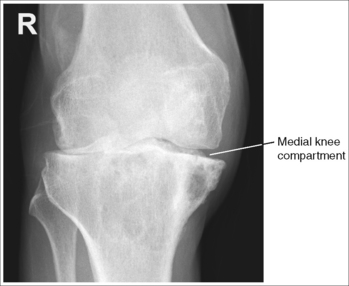

• Analysis of joint space narrowing. On an AP knee projection with adequate positioning, joint space narrowing is evaluated by measuring the medial and lateral aspects of the knee joint, which are also referred to as compartments. The measurement of each of these compartments is obtained by determining the distance between the most distal femoral condylar surface and the posterior condylar margin of the tibia on each side. Comparison of these measurements with each other, with measurements from previous images, or with measurements of the other knee determines joint space narrowing or a valgus or varus deformity. In a valgus deformity the lateral compartment is narrower than the medial compartment; in a varus deformity the medial compartment is narrower (see Images 56 and 57). Precise measurements of the compartments are necessary to ensure early detection of joint space narrowing and are best obtained when the knee joint space is completely open. If an inaccurate central ray angulation was used for an AP knee projection, the knee joint is narrowed or obscured, the intercondylar eminence and tubercles are foreshortened, and the tibial plateau is demonstrated.

IMAGE 56

The lateral knee compartment is narrower than the medial knee compartment. The patient's knee demonstrates a valgus deformity.

The medial knee compartment is narrower than the lateral knee compartment. The patient's knee demonstrates a varus deformity.